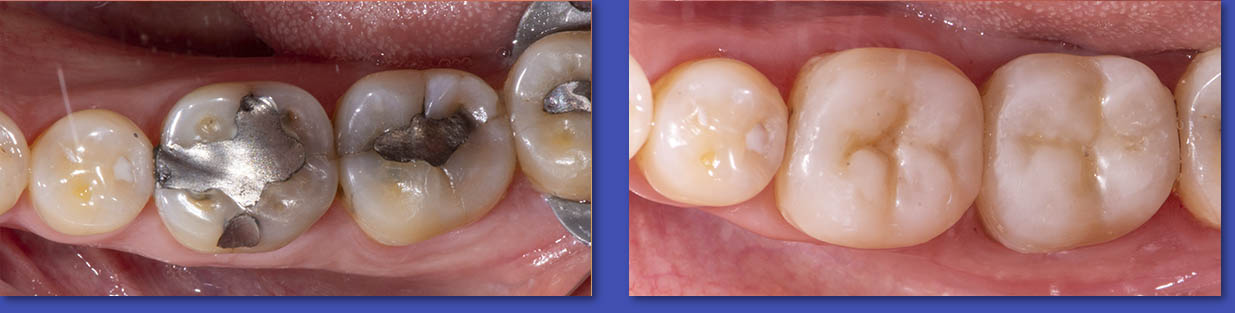

1.  OPERATORIA DENTAL

La Operatoria Dental se dedica a la restauración de los dientes dañados en forma parcial producto de caries, traumatismos  y otras lesiones no cariosas (atrición, abrasión, erosión, hipoplasias de esmalte, etc.). Hoy en día estas restauraciones se realizan en material de resina llamados “composite” que imitan el color del diente y han dejado casi obsoletas a las restauraciones metálicas y amalgamas.

ANTES

DESPUÉS